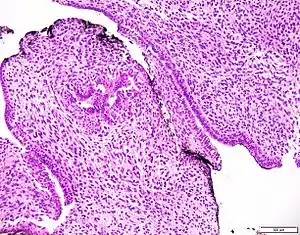

| Prostatic stromal tumour of uncertain malignant potential. H&E stain. | |